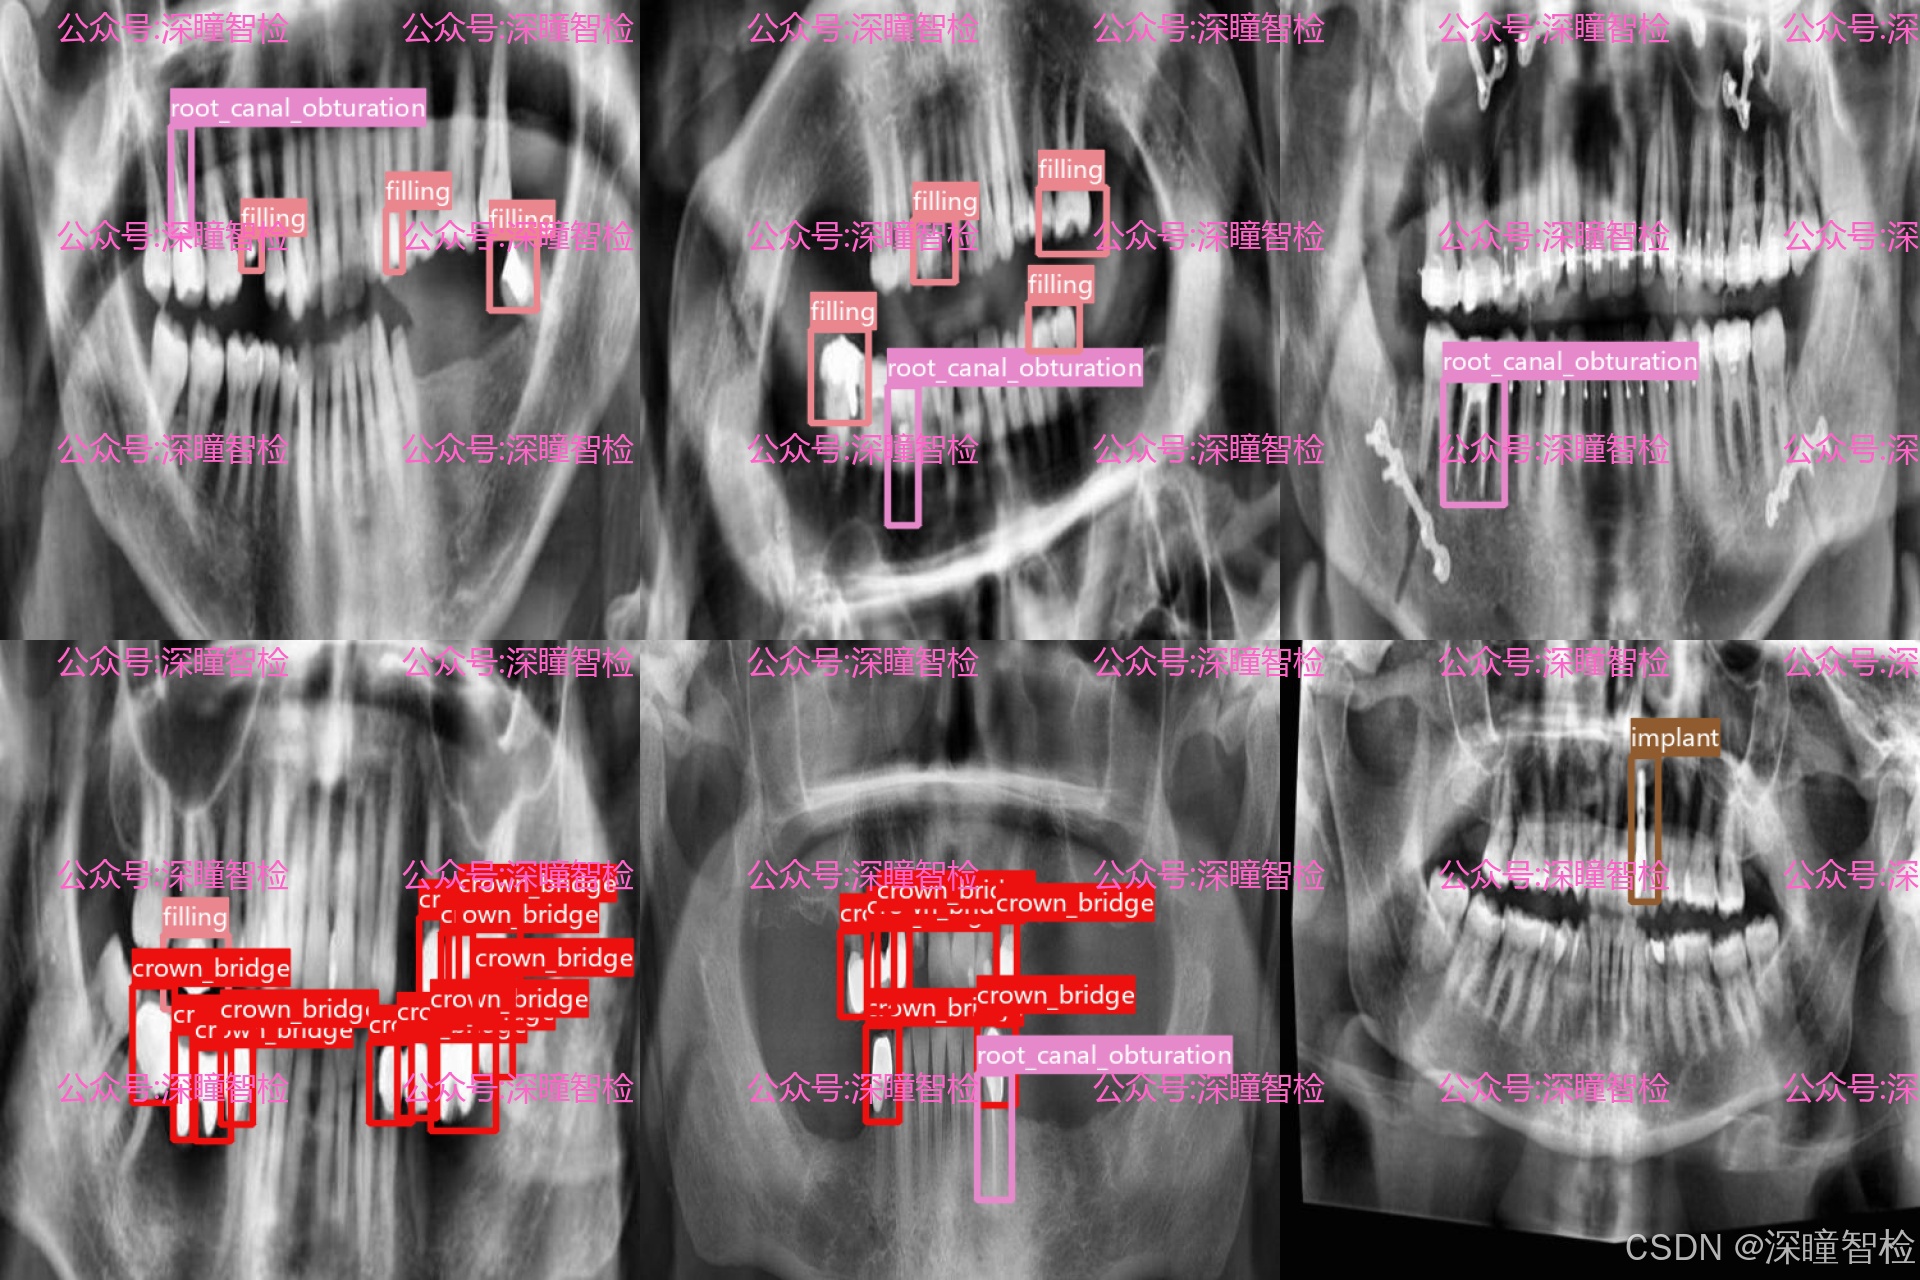

数据集围绕临床中常见的牙体修复及治疗后表现,定义了 4 类关键检测目标:

- • 充填物(filling):包含各类树脂、银汞等补牙材料影像,对应龋齿等牙体缺损的基础修复方式。

- • 冠桥修复体(crown_bridge):覆盖单冠、连冠及固定桥等修复体影像,对应牙体大面积缺损或缺失的修复方案。

- • 种植牙根(implant):包含植入颌骨内的种植体影像,对应牙列缺失的种植修复方式。

- • 根管充填物(root_canal_obturation):包含根管治疗后填充的牙胶尖等材料影像,对应牙髓病与根尖周病的治疗后表现。

每一类标注均由具备口腔医学背景的专业人员完成,通过多人交叉审核机制确保标注的准确性与一致性,为模型学习提供了高可信度的监督信号。